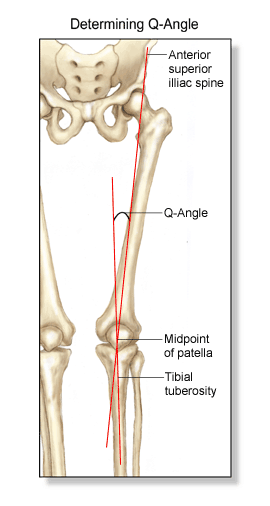

Ahora lo que debemos de saber es cuál es el eje de carga de nuestra pierna. Hay personas que tienen tendencia a tener las piernas en cruz, con las rodillas hacia dentro, muy frecuente en mujeres, son las denominadas rodillas valgas cuyo eje de carga suele coincidir en el compartimento externo de la rodilla. Otras son las que tienen las piernas arqueadas, con las rodillas hacia afuera, son las denominadas rodillas varas que suelen coincidir con un eje de carga sobre el compartimento interno, muy frecuentes en varones aunque también en mujeres mayores. Fijaros en muchos futbolistas por poner un ejemplo. Este tipo de sobrecarga interna es quizá la más frecuente. También hay muchas personas que tienen un eje de carga neutro donde se reparte el impacto de forma ordenada por los diferentes compartimentos de la rodilla. Es muy importante hacer aquí un apunte. Muchos ejes de carga que no son patológicos pueden acabar siéndolo por lesiones previas en estabilizadores de la rodilla como ligamentos o tendones.